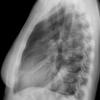

Case 2  Lingular pneum Lat

Date: 04/17/2005

Views: 6833